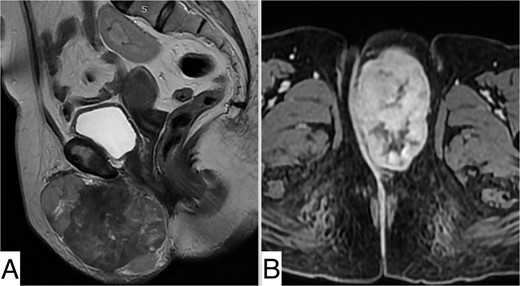

Upon physical examination, a well-defined mass spanning the left labia majora, measuring 10 cm in length, was noted. The mass was firm, non-tender, and mobile in the superficial plane but adherent to the deep plane (Fig. 1). The overlaying skin showed no inflammatory signs. There were no palpable lymph nodes, and pelvic examination was unremarkable.

Pelvic MRI revealed a well-defined, rounded mass centered on the left labia majora, isointense on T1 compared with muscle, heterogeneously enhanced after Gadolinium injection, indicating necrotic areas, measuring 98 × 57 × 77 mm. It was in close contact with the left ischiopubic ramus and infiltrated the lower two-thirds of the vesical urethra without invading it. It extended into the retro-pubic fat more markedly on the left. The right labium majus, clitoris, and adjacent perineal structures were preserved. The vagina, cervix, anal canal, and rectum were unaffected (Fig. 2).